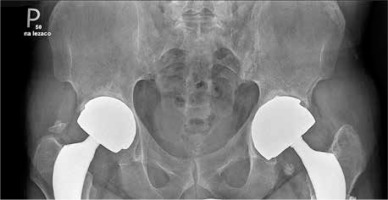

Fig. 1

X-ray of sacroiliac joints showing bilateral ankyloses typical for final stage of ankylosing spondylitis and two hip prostheses. The prostheses were implanted because of severe hip joint destruction caused by ankylosing spondylitis

Here, we describe a case of a 52-year-old man with long-standing ankylosing spondylitis (AS) with bilateral ankylosis of the sacroiliac joints, grade IV according to modified New York criteria (Fig. 1) with a history of peptic ulcer disease and no other comorbidities who developed seropositive rheumatoid arthritis (RA). The diagnosis of AS was made in 2006 and was based on a combination of inflammatory back pain, X-ray of the sacroiliac joints (bilateral grade III sacroiliitis at the time of diagnosis) and the presence of HLA-B27. He did not present peripheral arthritis, enthesitis, uveitis or psoriasis. At the time of diagnosis, inflammatory indicators were increased: C-reactive protein (CRP) 9.8 mg/l (normal value [NV] < 5 mg/l), erythrocyte sedimentation rate (ESR) 48 mm/h (NV < 12 mm/h]) but rheumatoid factor (RF) and anti-citrullinated peptides antibodies (ACPA) were absent. Baseline disease activity measured with Bath Ankylosing Spondylitis Disease Activity Index (BASDAI) was high: 8.6. Initially, the patient was treated with non-steroidal anti-inflammatory drugs (NSAIDs) for 6 years. Since NSAIDs ceased to control the disease activity in 2012, etanercept was introduced. He had undergone left (2013) and right (2014) hip arthroplasty due to severe secondary coxarthrosis in the course of AS. Because of worsening of spinal pain and stiffness, significant deterioration in mobility, and persistent systemic inflammation (ESR 52 mm/h, CRP 102 mg/l) etanercept was replaced with secukinumab in January 2020. In February 2020, after two doses of secukinumab, the patient was admitted to the tertiary rheumatology center with acute symmetric polyarthritis of new-onset involving shoulders, elbows, wrists, small joints of the hands, feet, and knees with pain scored 10/10 on the Visual Analogue Scale (VAS). Inflammatory indicators were increased: CRP 35 mg/l, ESR 73 mm/h. X-rays of the hands and feet did not reveal abnormalities. Ultrasound of the joints revealed (according to the OMERACT recommendations): GS = 1, PD = 1 bilaterally in the wrist joints, GS = 1 + effusion, PD = 0 (left hand III PIP); tenosynovitis in the fourth extensor compartment of the right hand (GS = 1 + effusion, PD = 0). Systemic steroid therapy was started and NSAIDs were maintained, resulting in a transient clinical improvement. At 2 months of follow-up polyarthritis with symmetric involvement of the wrists was still present. Autoantibodies were detected: ACPA 500 IU/ml (NV < 8), RF 379 IU/ml (NV < 15). Therefore, the patient was diagnosed with RA according to the ACR/EULAR 2010 criteria [1]. Treatment with the JAK inhibitor tofacitinib was initiated in July 2021. Despite treatment, symmetric polyarthritis of the hands persisted. Follow-up X-rays of the hands showed juxta-articular osteoporosis and inflammatory cysts in the joints that were most affected by ultrasound (Fig. 2). In December 2021 tofacitinib was switched to anti-interleukin (IL)-6 tocilizumab, which caused substantial clinical improvement and allowed remission of RA along with sustained remission of AS. Treatment modifications and disease activity are presented in Table 1. Comparison of RA and AS diagnosis and treatment is presented in Table 2. After 18 months of tocilizumab treatment, both RA and AS remain in remission (DAS-28 1.2, BASDAI 2.0, ESR 1 mm/h, CRP 1 mg/l).